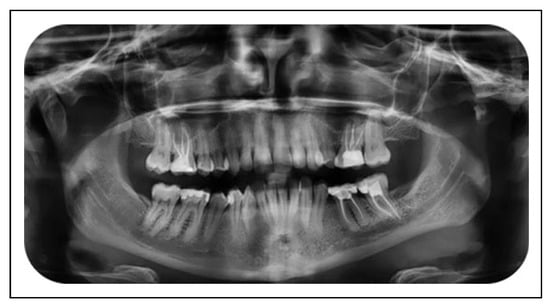

Reduced mouth opening is a complaint in 8-10% of all condylar fractures and is usually present immediately after trauma but can persevere and worsen over time. Early mobilization should be considered to avoid reduced mouth opening, even at the expense of a stable occlusion.[16,17] The longer the period of IMF, the more hypo-mobility is described.[13] Different causes of reduced mouth opening as a long-term complication have been described, including intracranial condyle, condylar sag, condylar resorption, bifid condyle, non-union, and ankylosis. An intracranial condyle is a rare condition caused by a high energetic trauma. A literature review revealed 51 previous cases in the English language.[18] Condylar sag was first described by Hall in 1975 and can be described as a change in the position of the condyle in the glenoid fossa after establishing a proper occlusion.[19,20,21] In 1 patient suffering from reduced mouth opening, condylar sag was thought to be the cause (Figure 1 and Figure 2).

Figure 1. Condylar sag of the left condyle, panoramic dental x-ray.